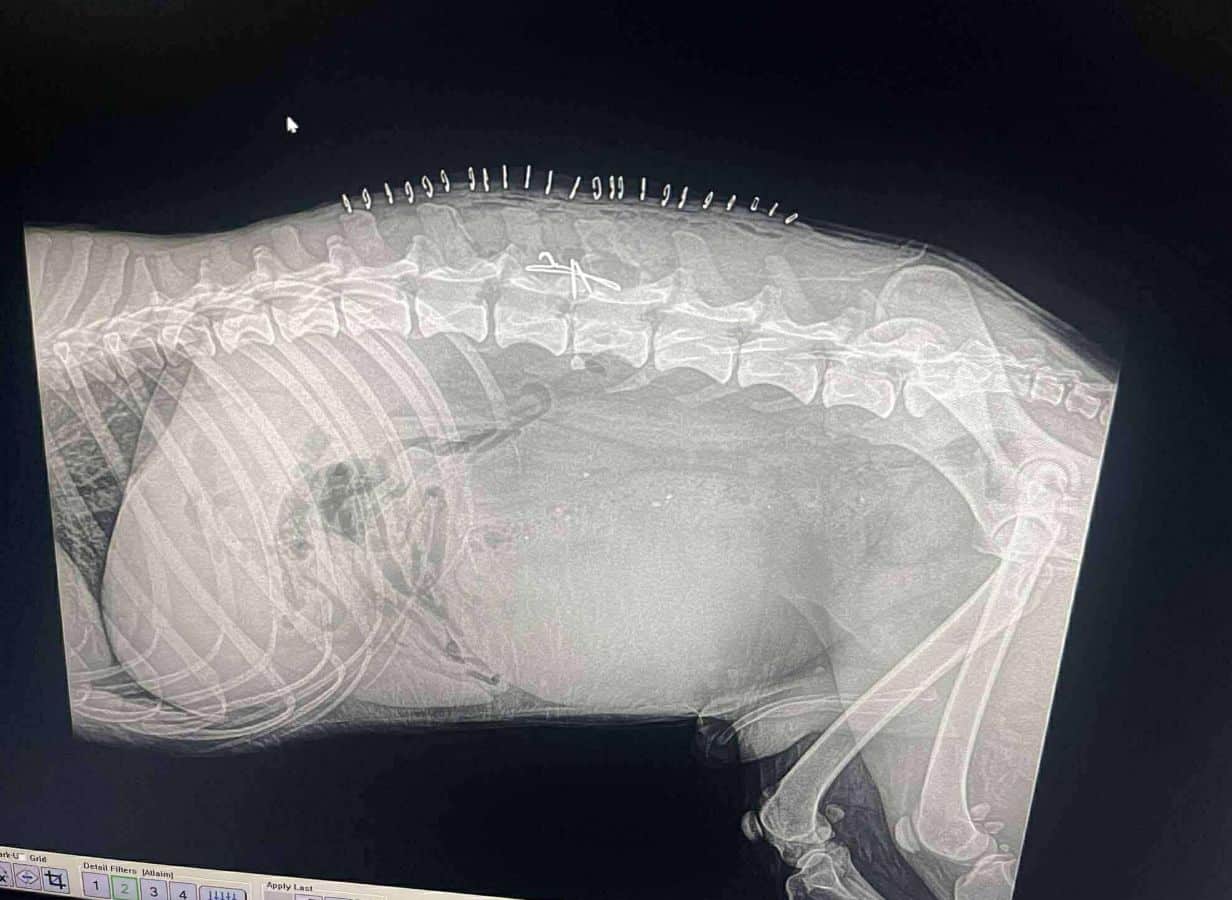

Unser Tierschützer entdeckte diese arme Seele schwer verletzt und hilflos am Straßenrand. Er nahm ihn mit und rettete ihm damit vermutlich das Leben. In der Tierklinik wurde MAJEED geröntgt und an der Wirbelsäule operiert.

Noch ist unklar, welche Auswirkungen die Operation langfristig haben wird und inwieweit er später durch seinen Bewegungsapparat oder eine mögliche Beeinträchtigung der Blasen- und Darmkontrolle eingeschränkt sein könnte. Leider wurde er auch positiv auf Herzwürmer getestet und wird derzeit entsprechend behandelt.

In Deutschland wird MAJEED viel Physiotherapie brauchen, was ihm enorm helfen würde, da gezielte Bewegungseinheiten seine Muskulatur stärken, die Mobilität fördern und die Genesung seiner Wirbelsäule unterstützen können. Für ihn wäre daher eine schnelle Ausreise wichtig, denn je länger er dort unbewegt liegt, desto schlechter wird es für ihn.